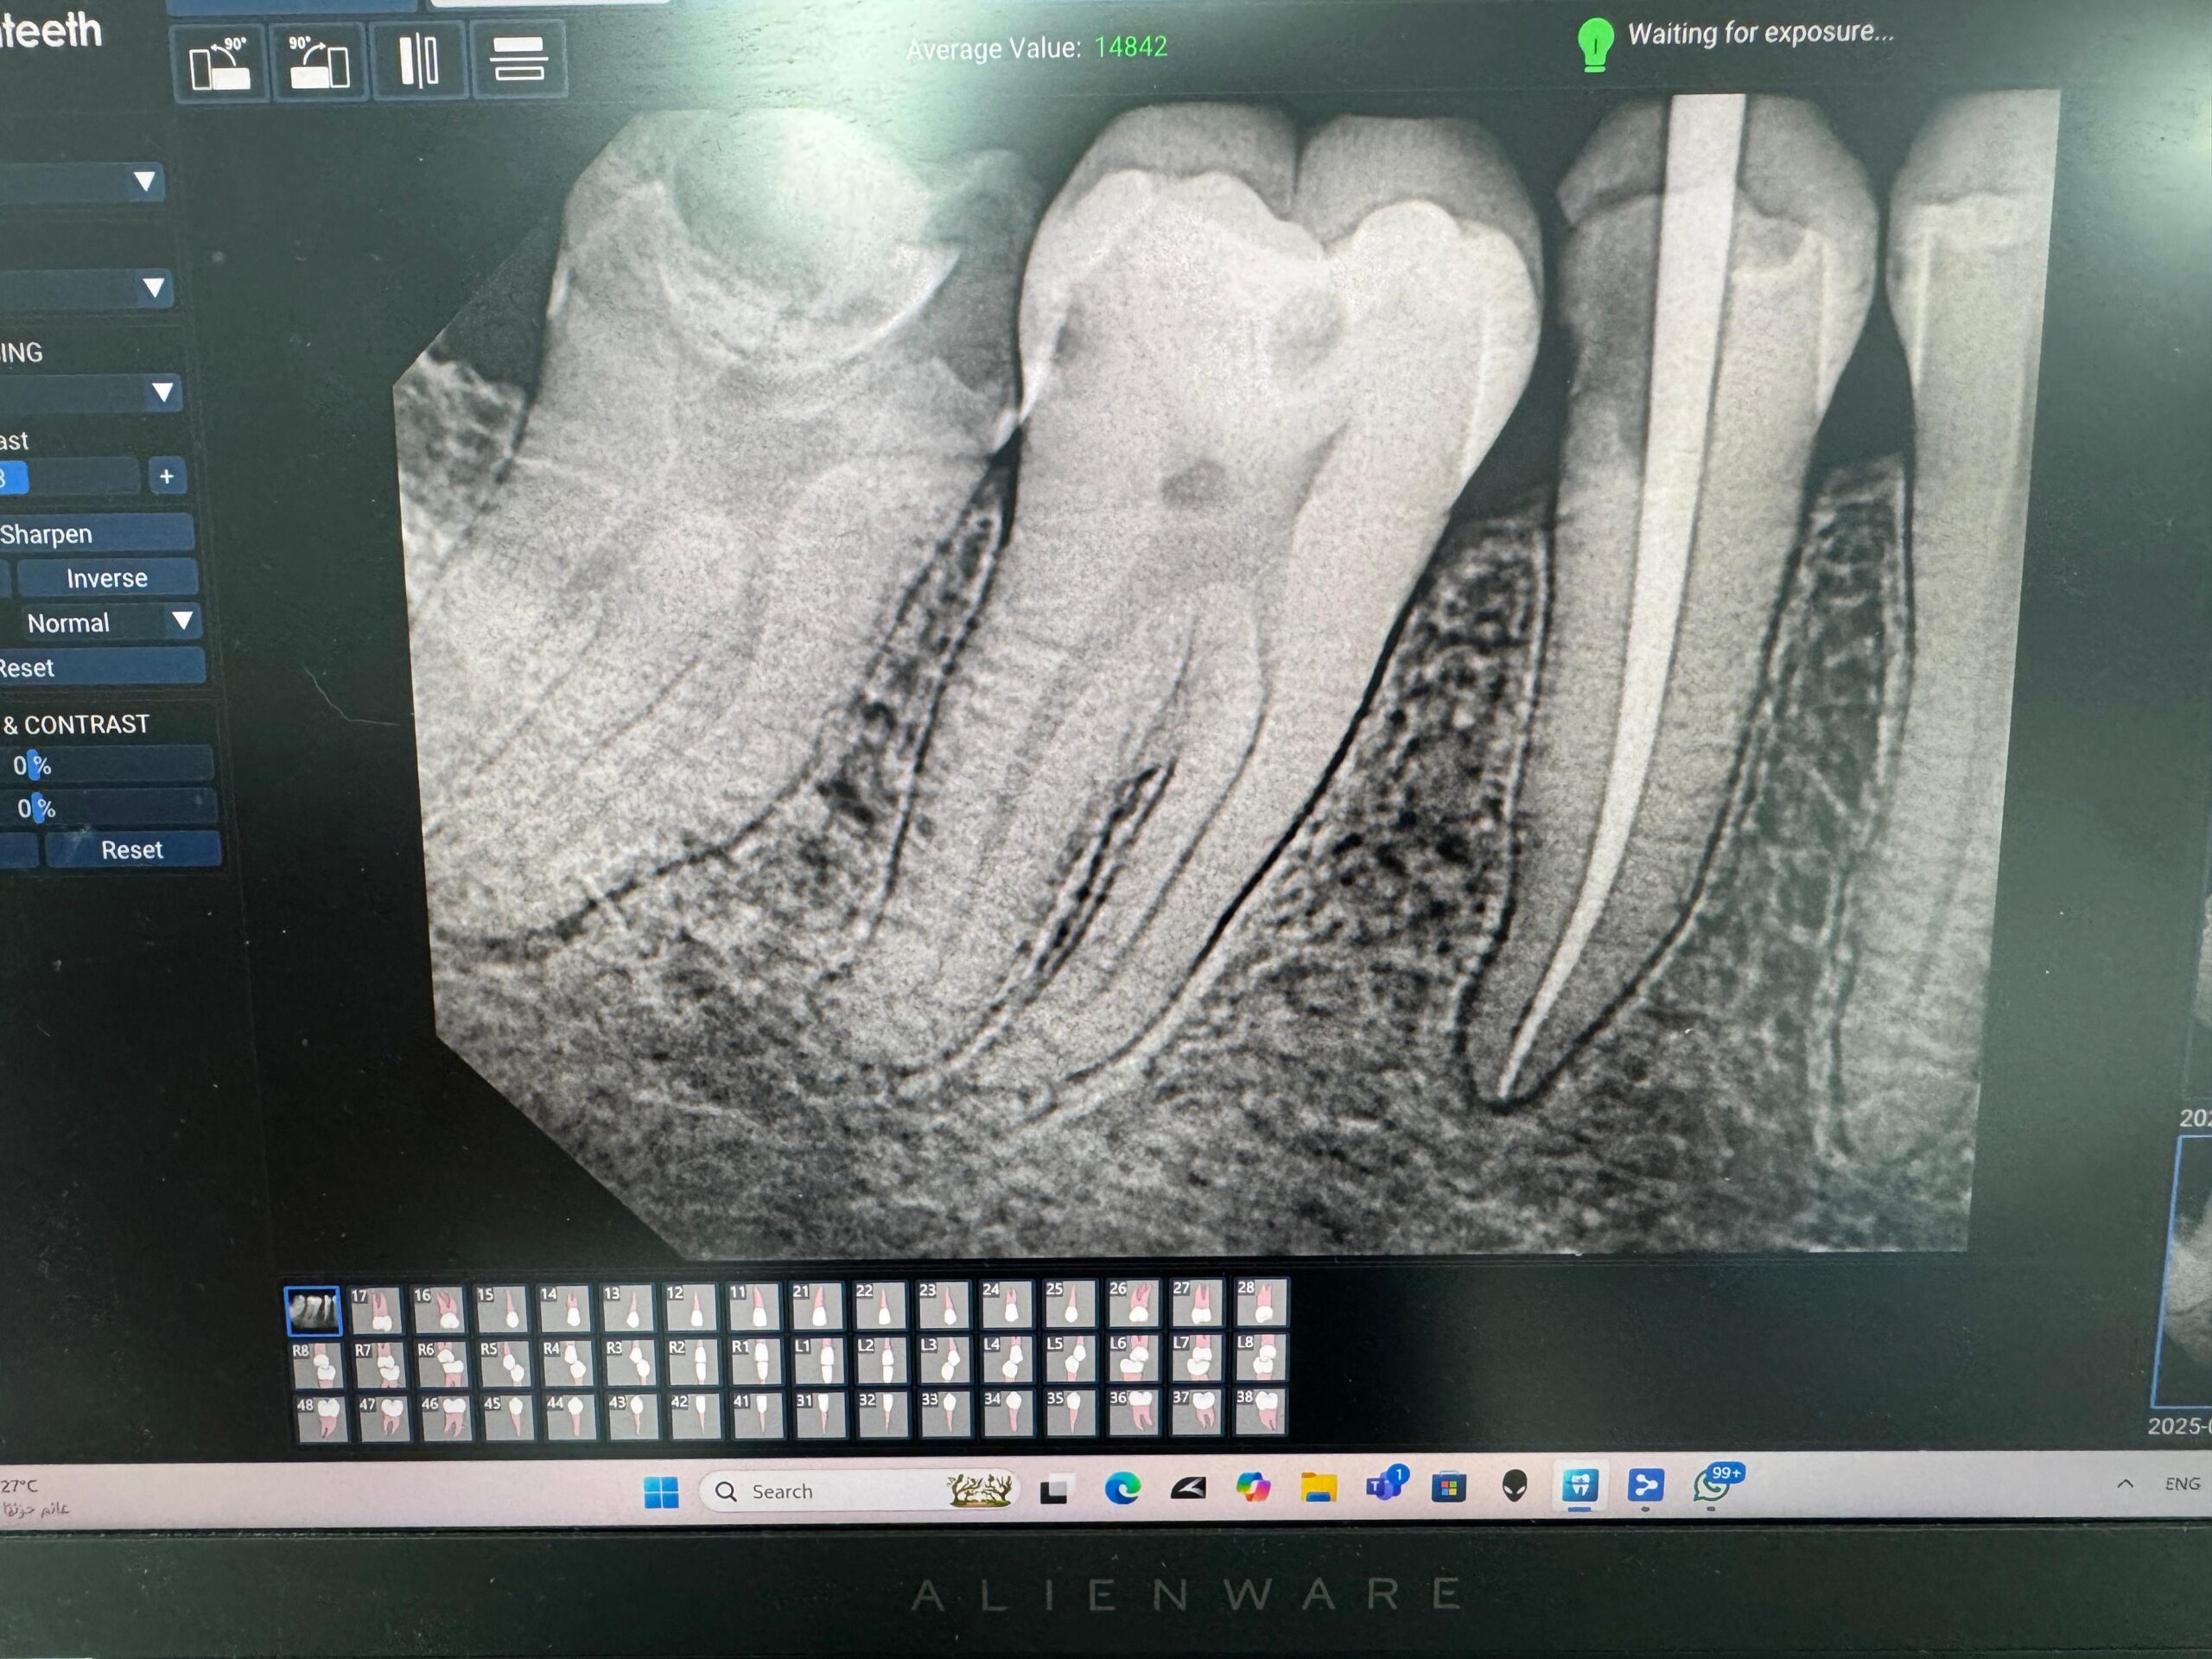

• Accurate diagnosis of nerve condition using the latest radiology equipment.

• Using modern root canal filling devices to ensure accurate and efficient cleaning of the nerve canals.

• Extensive experience in treating complex cases such as chronic nerve inflammation or tortuous canals.